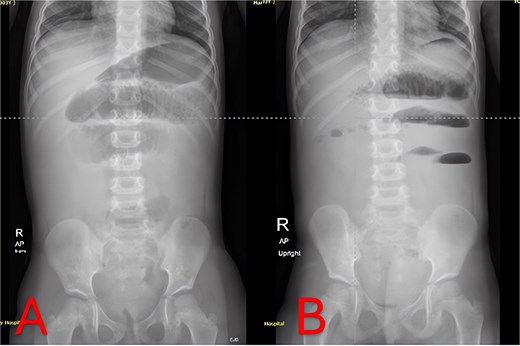

Plain abdominal radiographs revealed centrally dilated small-bowel loops with paucity of distal gas (Fig. 1A) and multiple air–fluid levels without free subdiaphragmatic air (Fig. 1B), consistent with mechanical small-bowel obstruction. Initial management, including nasogastric decompression, nil per os (NPO) status, and intravenous ceftriaxone (75 mg/kg once daily) plus vancomycin (15 mg/kg every 6 hours), failed to improve radiographic findings after 24 hours (Fig. 2A and B), prompting further imaging.

Admission abdominal radiographs (composite). (A) Supine abdominal X-ray on presentation demonstrating central small-bowel dilation and paucity of distal gas. (B) Upright abdominal X-ray on presentation showing multiple small-bowel air-fluid levels without free air.